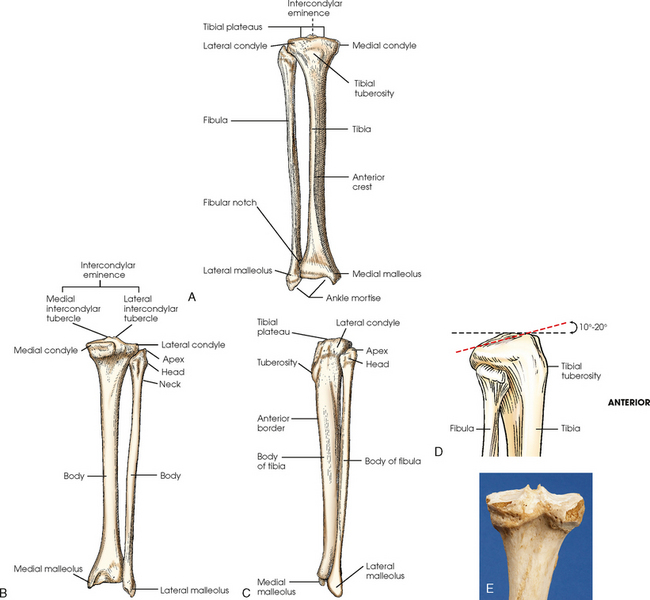

The tibia (Fig. 6-4) is the larger of the two bones of the leg and consists of one body and two expanded extremities. The proximal end of the tibia has two prominent processes—the medial and lateral condyles. The superior surfaces of the condyles form smooth facets for articulation with the condyles of the femur. These two flatlike superior surfaces are called the tibial plateaus, and they slope posteriorly about 10 to 20 degrees. Between the two articular surfaces is a sharp projection, the intercondylar eminence, which terminates in two peaklike processes called the medial and lateral intercondylar tubercles. The lateral condyle has a facet at its distal posterior surface for articulation with the head of the fibula. On the anterior surface of the tibia, just below the condyles, is a prominent process called the tibial tuberosity, to which the ligamentum patellae attach. Extending along the anterior surface of the tibial body, beginning at the tuberosity, is a sharp ridge called the anterior crest.

Fig. 6-4 Right tibia and fibula. A, Anterior aspect. B, Posterior aspect. C, Lateral aspect. D, Proximal end of tibia and fibula showing angle of tibial plateau. E, Photograph of superior and posterior aspect of the tibia.

The fibula is slender compared with its length and consists of one body and two articular extremities. The proximal end of the fibula is expanded into a head, which articulates with the lateral condyle of the tibia. At the lateroposterior aspect of the head is a conic projection called the apex. The enlarged distal end of the fibula is the lateral malleolus. The lateral malleolus is pyramidal and marked by several depressions at its inferior and posterior surfaces. Viewed axially, the lateral malleolus lies approximately 15 to 20 degrees more posterior than the medial malleolus (see Fig. 6-5, C).